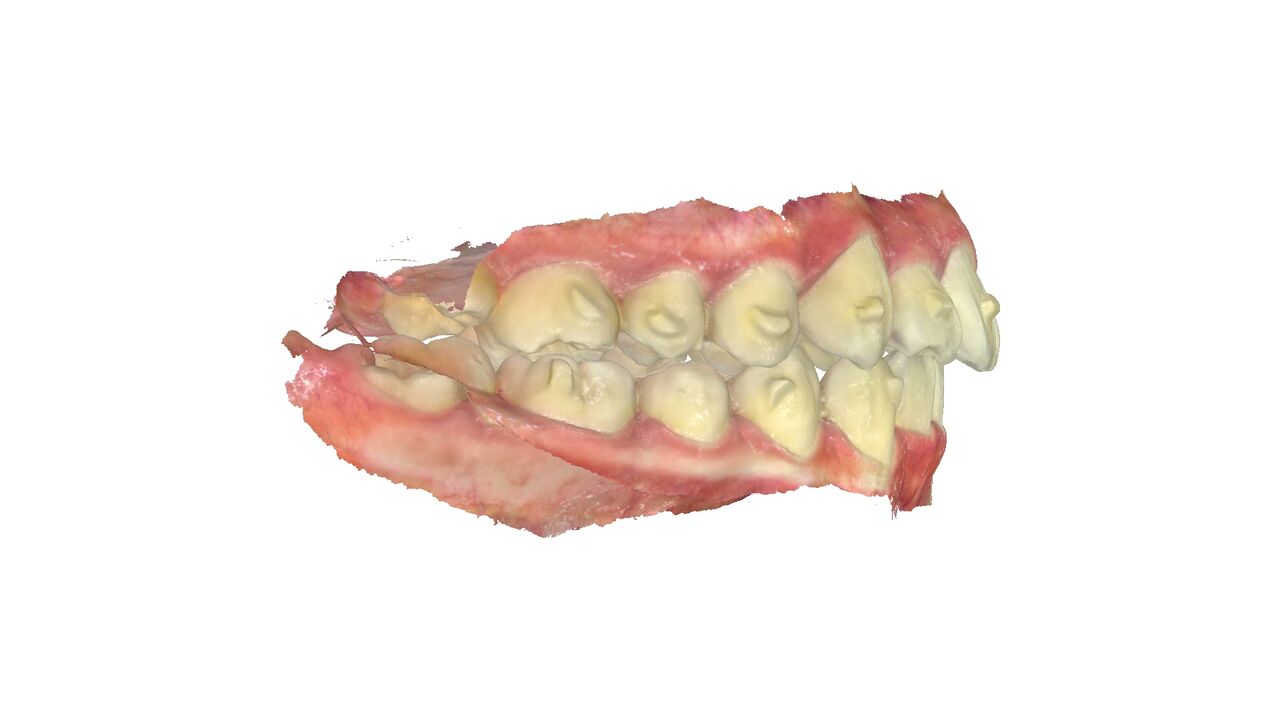

横から見ると少し前歯が出っ歯気味になっている。

横からは、やや出っ歯だったのが、出っ歯感はなくなった。